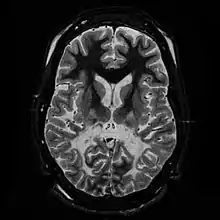

White matter, with reduced volume and increased signal intensity. The anterior white matter is spared. Features are consistent with X-linked adrenoleukodystrophy.